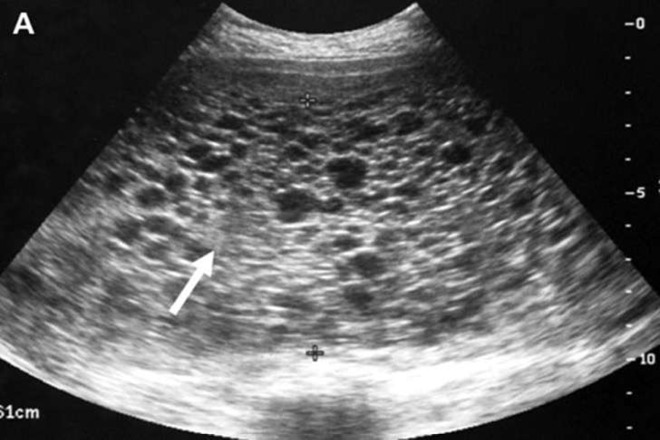

El diagnóstico se confirma con estudios básicos como la ecografía y análisis de sangre que miden la hormona hCG, la cual suele encontrarse en niveles muy elevados, una vez identificado, el tratamiento consiste en retirar el tejido anormal del útero y vigilar cuidadosamente la evolución de la paciente.